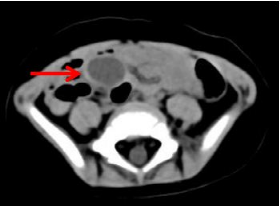

2、CT检查:对于囊肿型肠重复畸形,CT表现有一定特征性:可见紧贴消化道的类圆形囊状低密度影,囊腔张力高,边缘清晰,边缘清晰,部分囊壁呈分层状,内层密度稍低,外层稍高,呈“晕轮征”;增强后囊壁均匀强化,“晕轮征”显示更加清楚。

undefined

上图为肠重复畸形的CT平扫,可见一囊肿(红色箭头所指)